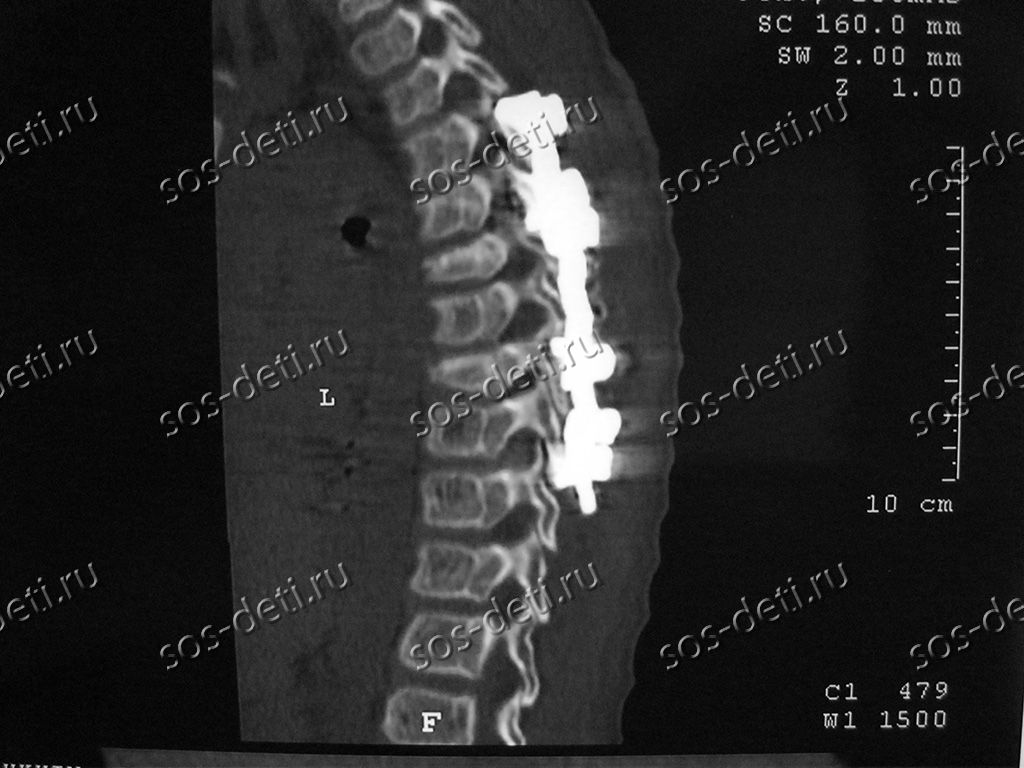

Сергею 13 лет, он из г. Белоусово Калужской области. Его диагноз – компрессионный оскольчатый нестабильный перелом Th6, Th8 тел позвонков 3 степени. В Государственном бюджетном учреждении здравоохранения «Калужская областная детская больница» ему по экстренным медицинским показаниям установили имплантаты стабилизации позвоночника Medtronic (США). Оплата имплантатов за счет бюджетных средств не производится. Стоимость базовой комплектации имплантатов, блоков и гранул для регенерации костной ткани составила 432 580 рублей.

1 июля Сергей катался на качелях и упал вниз головой. После падения был направлен в медсанчасть г. Обнинска. Должного обследования и лечения получить не удалось и 9 июля Сергея привезли в травматолого-ортопедическое отделение Калужской областной детской больницы, где сразу установили диагноз и приняли решение об операции. 10 июля по экстренным медицинским показаниям выполнена операция задней стабилизации позвоночника на уровне 5-6-7-8-9 грудных позвонков конструкцией Medtronic Sofamor Danek (США). Имплантаты закупает для клиники Фонд и при экстренных случаях поставщик всегда идет навстречу и привозит необходимые имплантаты и инструменты ко дню операции в долг (под гарантию последующей оплаты Фондом). Это уже не первый случай. При таких обстоятельствах были прооперированы Никита Кривчиков, Никита Пронин, Дмитрий Левенец.

Сергею выполнена операция задней стабилизации позвоночника на уровне 5-6-7-8-9 грудных позвонков конструкцией Medtronic (США). Операция прошла успешно, положение имплантатов стабильное. Ближайшие два дня мальчик пробудет в реанимации под наблюдением врачей.

Сергей поступил в отделение травматологии и ортопедии Калужской областной детской больницы из медсанчасти города Обнинска в состоянии средней тяжести. В течении 9 (!!!) дней обнинские врачи не смогли правильно диагностировать и оказать необходимую помощь мальчику и на скорой помощи отправили его в Калугу. При поступлении у Сергея наблюдались боли в грудном отделе, ярко выражено искривление среднегрудного отдела позвоночника. Врачи сразу сделали Сергею компьютерную томографию и рентген, был установлен диагноз: компрессионный оскольчатый нестабильный перелом Th6, Th8 тел позвонков 3 степени. Промедление с оперативным лечением могло вызвать серьезные осложнения, поэтому было принято решение о проведении экстренной операции по жизненным показаниям на завтра.